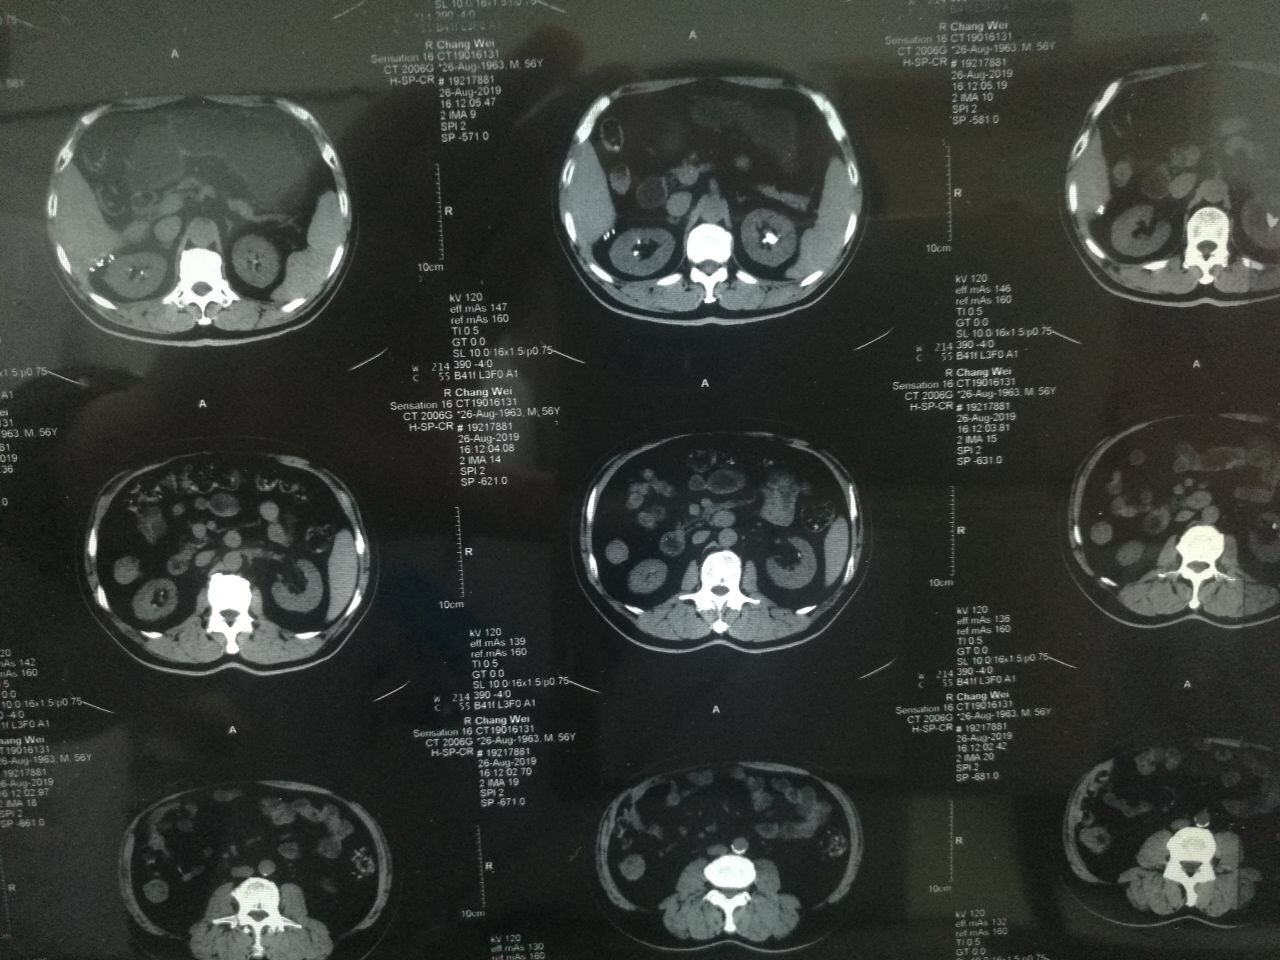

?2019年8月22日,家住陕西永寿县的一岁半幼儿笑笑(化名)突然出现阵发性哭闹,且伴有腹痛、小便不畅、尿色深黄浑浊等症状,奶奶遂带其前往永寿县医院诊治,县医院诊断为“包皮炎”,并给予局部涂擦碘伏。可没想到5天后,笑笑再次哭闹不止,且完全不能自解小便,尿液自尿道溢出,下腹胀满。再次来到县医院治疗,经过CT及超声检查显示,孩子尿潴留,尿道结石,肾结石。由于患儿年纪小,病情更为复杂和紧急,经推荐笑笑从县医院转入啄木鸟 泌尿外科进行治疗。转入啄木鸟 时,患儿腹胀如鼓,时不时有尿液自尿道滴出,哭闹异常剧烈。见此情景,泌尿外科张争春医生立即带领王卫妮护士长给患儿进行导尿,但因结石恰好卡在尿道,导尿管难以插入,张争春医生在患儿的哭闹声中,经过多次努力,终于将导尿管成功插入,暂时缓解了患儿的危急症状,也为后续的治疗创造了机会。